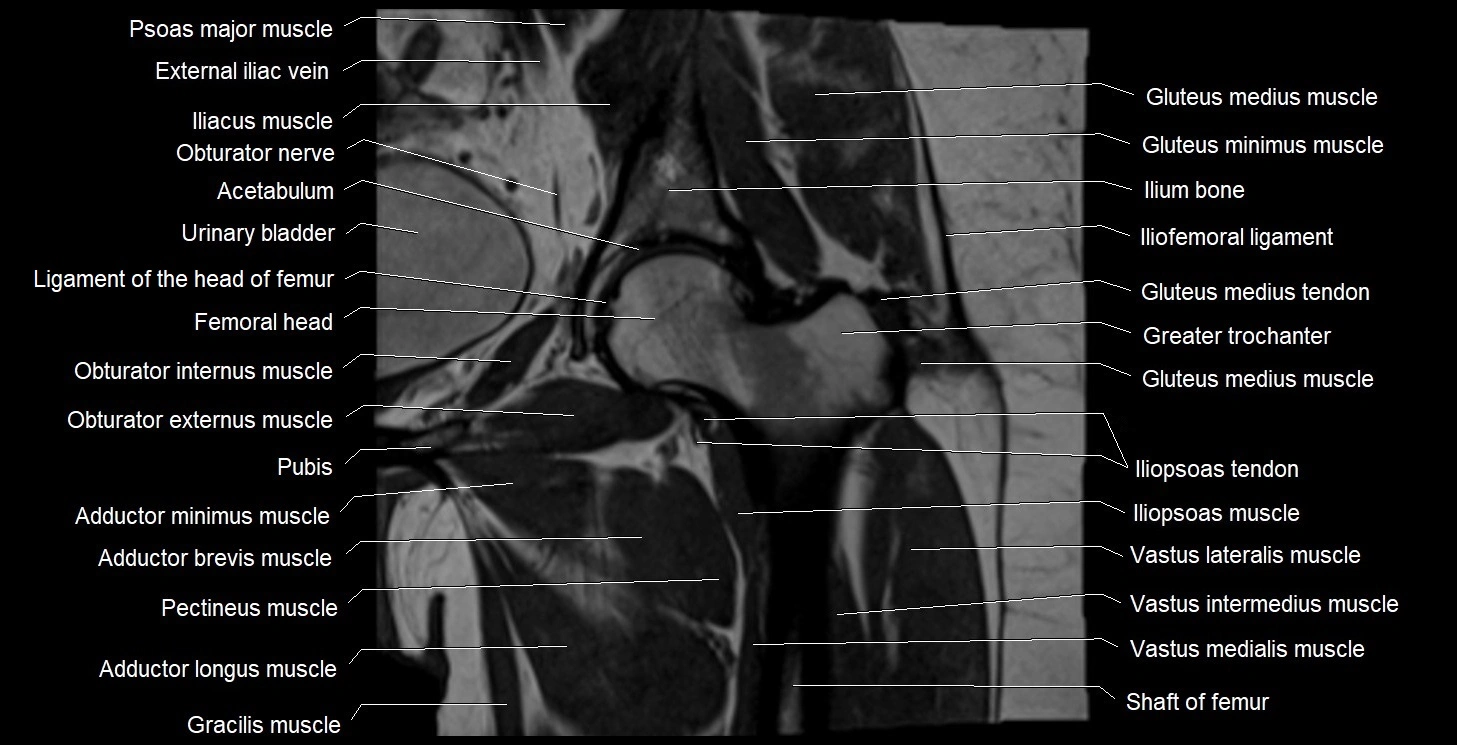

- Adductor brevis muscle

- Adductor longus muscle

- Adductor minimus muscle

- Femoral nerve

- Gluteus medius muscle

- Gluteus medius tendon

- Gluteus minimus muscle

- Gluteus minimus tendon

- Gracilis muscle

- Greater trochanter

- Head of femur

- Iliofemoral ligament

- Iliopsoas muscle

- Iliopsoas tendon

- Ilium bone

- Ligamentum teres (ligament of the head of femur)

- Obturator externus muscle

- Obturator internus muscle

- Obturator nerve

- Pectineus muscle

- Psoas major muscle

- Rectum

- Urinary bladder

- Vastus intermedius muscle

- Vastus lateralis muscle

- Vastus medialis muscle